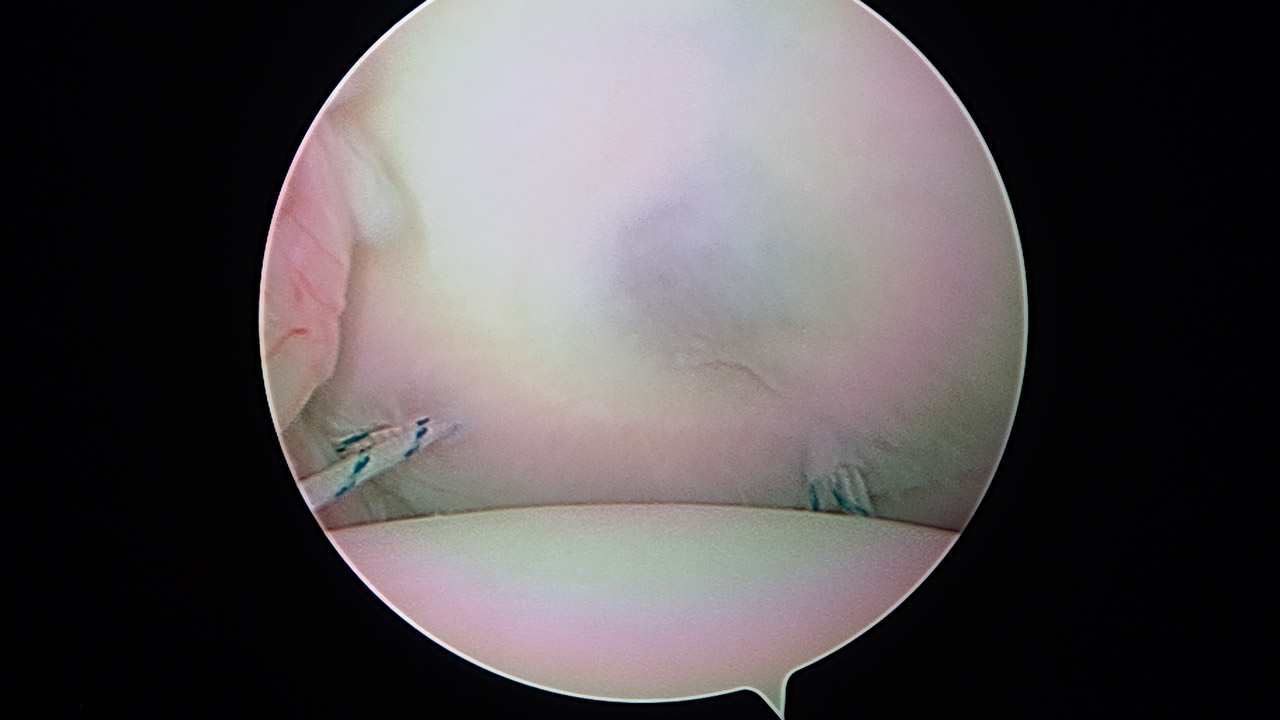

Presentamos una técnica quirúrgica artroscópica para los casos de inestabilidad traumática o atraumática de hombro, con hiperlaxitud multidireccional asociada, en los que hayan fracasado los tratamientos conservadores u otras técnicas quirúrgicas de plicatura capsular, y no presenten déficit óseo importante. Consiste en la plicatura del ligamento glenohumeral inferior (anteroinferior y posteroinferior) y la realización de una ligamentoplastia de refuerzo anterior artroscópica con aloinjerto en disposición transubescapular.

We present an arthroscopic surgical technique for cases of traumatic instability or atraumatic of the shoulder, with associated multidirectional hyperlaxity in which conservative treatments have failed, or other surgical techniques of plication capsular, and do not present major bone deficits. It consists of the plication of the lower glenohumeral ligament (anteroinferior and posteroinferior) and the accomplishment of an arthroscopic anterior reinforcement ligamentoplasty with allograft in a trans-scapular arrangement.